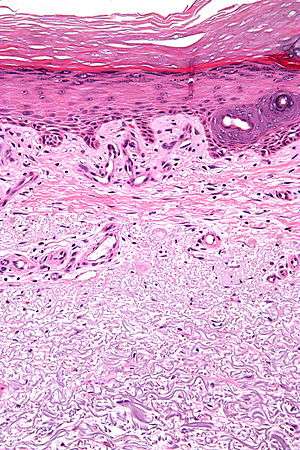

Micrograph showing solar elastosis - grey, jumbled spaghetti-like material on bottom of image. H&E stain.

In the earlier stages of actinic elastosis, elastic fiber proliferation can be seen in the dermis. As the condition becomes more established, the collagen fibers of the papillary dermis and reticular dermis become increasingly replaced by thickened and curled fibers that form tangled masses and appear basophilic under routine haematoxylin and eosin staining. These fibers stain black with the Verhoeff stain.[1]